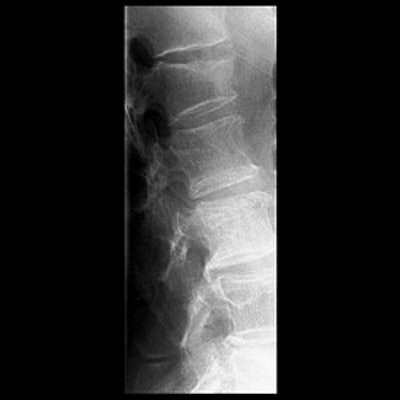

Top, radiography of a compression fracture. Center, vertebroplasty needle insertion. Below, post-procedure. Images courtesy of Dr. Martin Radvany.